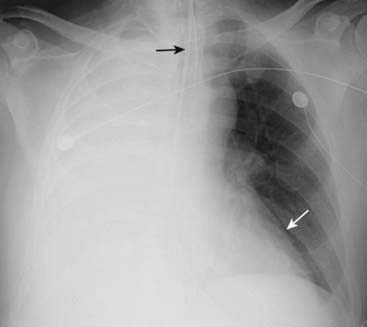

Figure 5-3 Atelectasis of the left lung.

There is complete opacification of the left hemithorax with shift of the trachea (solid black arrow) and the esophagus (marked here by a nasogastric tube, dotted black arrow) toward the side of the atelectasis. The right heart border, which should project about a centimeter to the right of the spine, has been pulled to the left side and is no longer visible. The patient had an obstructing bronchogenic carcinoma in the left main bronchus.

Figure 5-4 Atelectasis of the right lung.

There is complete opacification of the right hemithorax with shift of the trachea (solid black arrow) toward the side of the atelectasis. The left heart border is displaced far to the right and now almost overlaps the spine (solid white arrow). This patient had an endobronchial metastasis in the right main bronchus from her left-sided breast cancer. Did you notice the left breast was surgically absent?